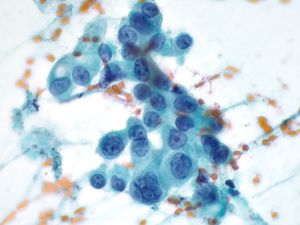

Benign Pancreas – PPANC4-04 Key Cytological Features of benign acinar cells:

- Cohesive, grape-like aggregates singly and attached to fibrovascular stroma

- Scattered stripped naked nuclei

- Basally located round nucleus

- Finely granular chromatin

- Small nucleolus; larger in reactive acinar cells

- Abundant granular cytoplasm

- Indistinct cell borders in clusters